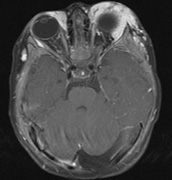

Cataracts in NF2 were recognized in 1986.97 They are common, reported to be found in 69%,98 81%,91 85%,99 and 87%100of cases. They are typically mild98 and a lens opacity may be the initial manifestation of disease, as found in 10% (5 of 49 patients) in one study.98

Retinal hamartomas affect about 10% to 20% of patients (8% in one study91and 22% in another98) and may be associated with a more severe phenotype of NF2.91,98 Combined pigment epithelial and retinal hamartomas (CPERH) and epiretinal membranes have been reported.101–103 Lisch nodules are rare in NF2. The absence of Lisch nodules, in association with the presence of posterior subcapsular or cortical cataracts (Fig. 8) may aid the differentiation of NF1 and NF2.97,104,105 Optic nerve sheath meningiomas may cause significant visual impairment in the first years of life (Table 2).84,106